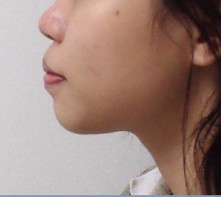

- Răng hô nặng: Với trường hợp răng hô nặng, bệnh nhân có thể phải nhổ từ 2 – 4 răng để tạo khoảng trống giúp kéo răng hô về đúng vị trí trên cung hàm.

- Răng móm: Tương tự như răng hô, với trường hợp răng móm nặng, người bệnh cũng phải nhổ bỏ một số răng không cần thiết trên cung hàm. Nhờ đó đảm bảo quá trình dịch chuyển của răng diễn ra nhanh chóng, thuận lợi hơn.